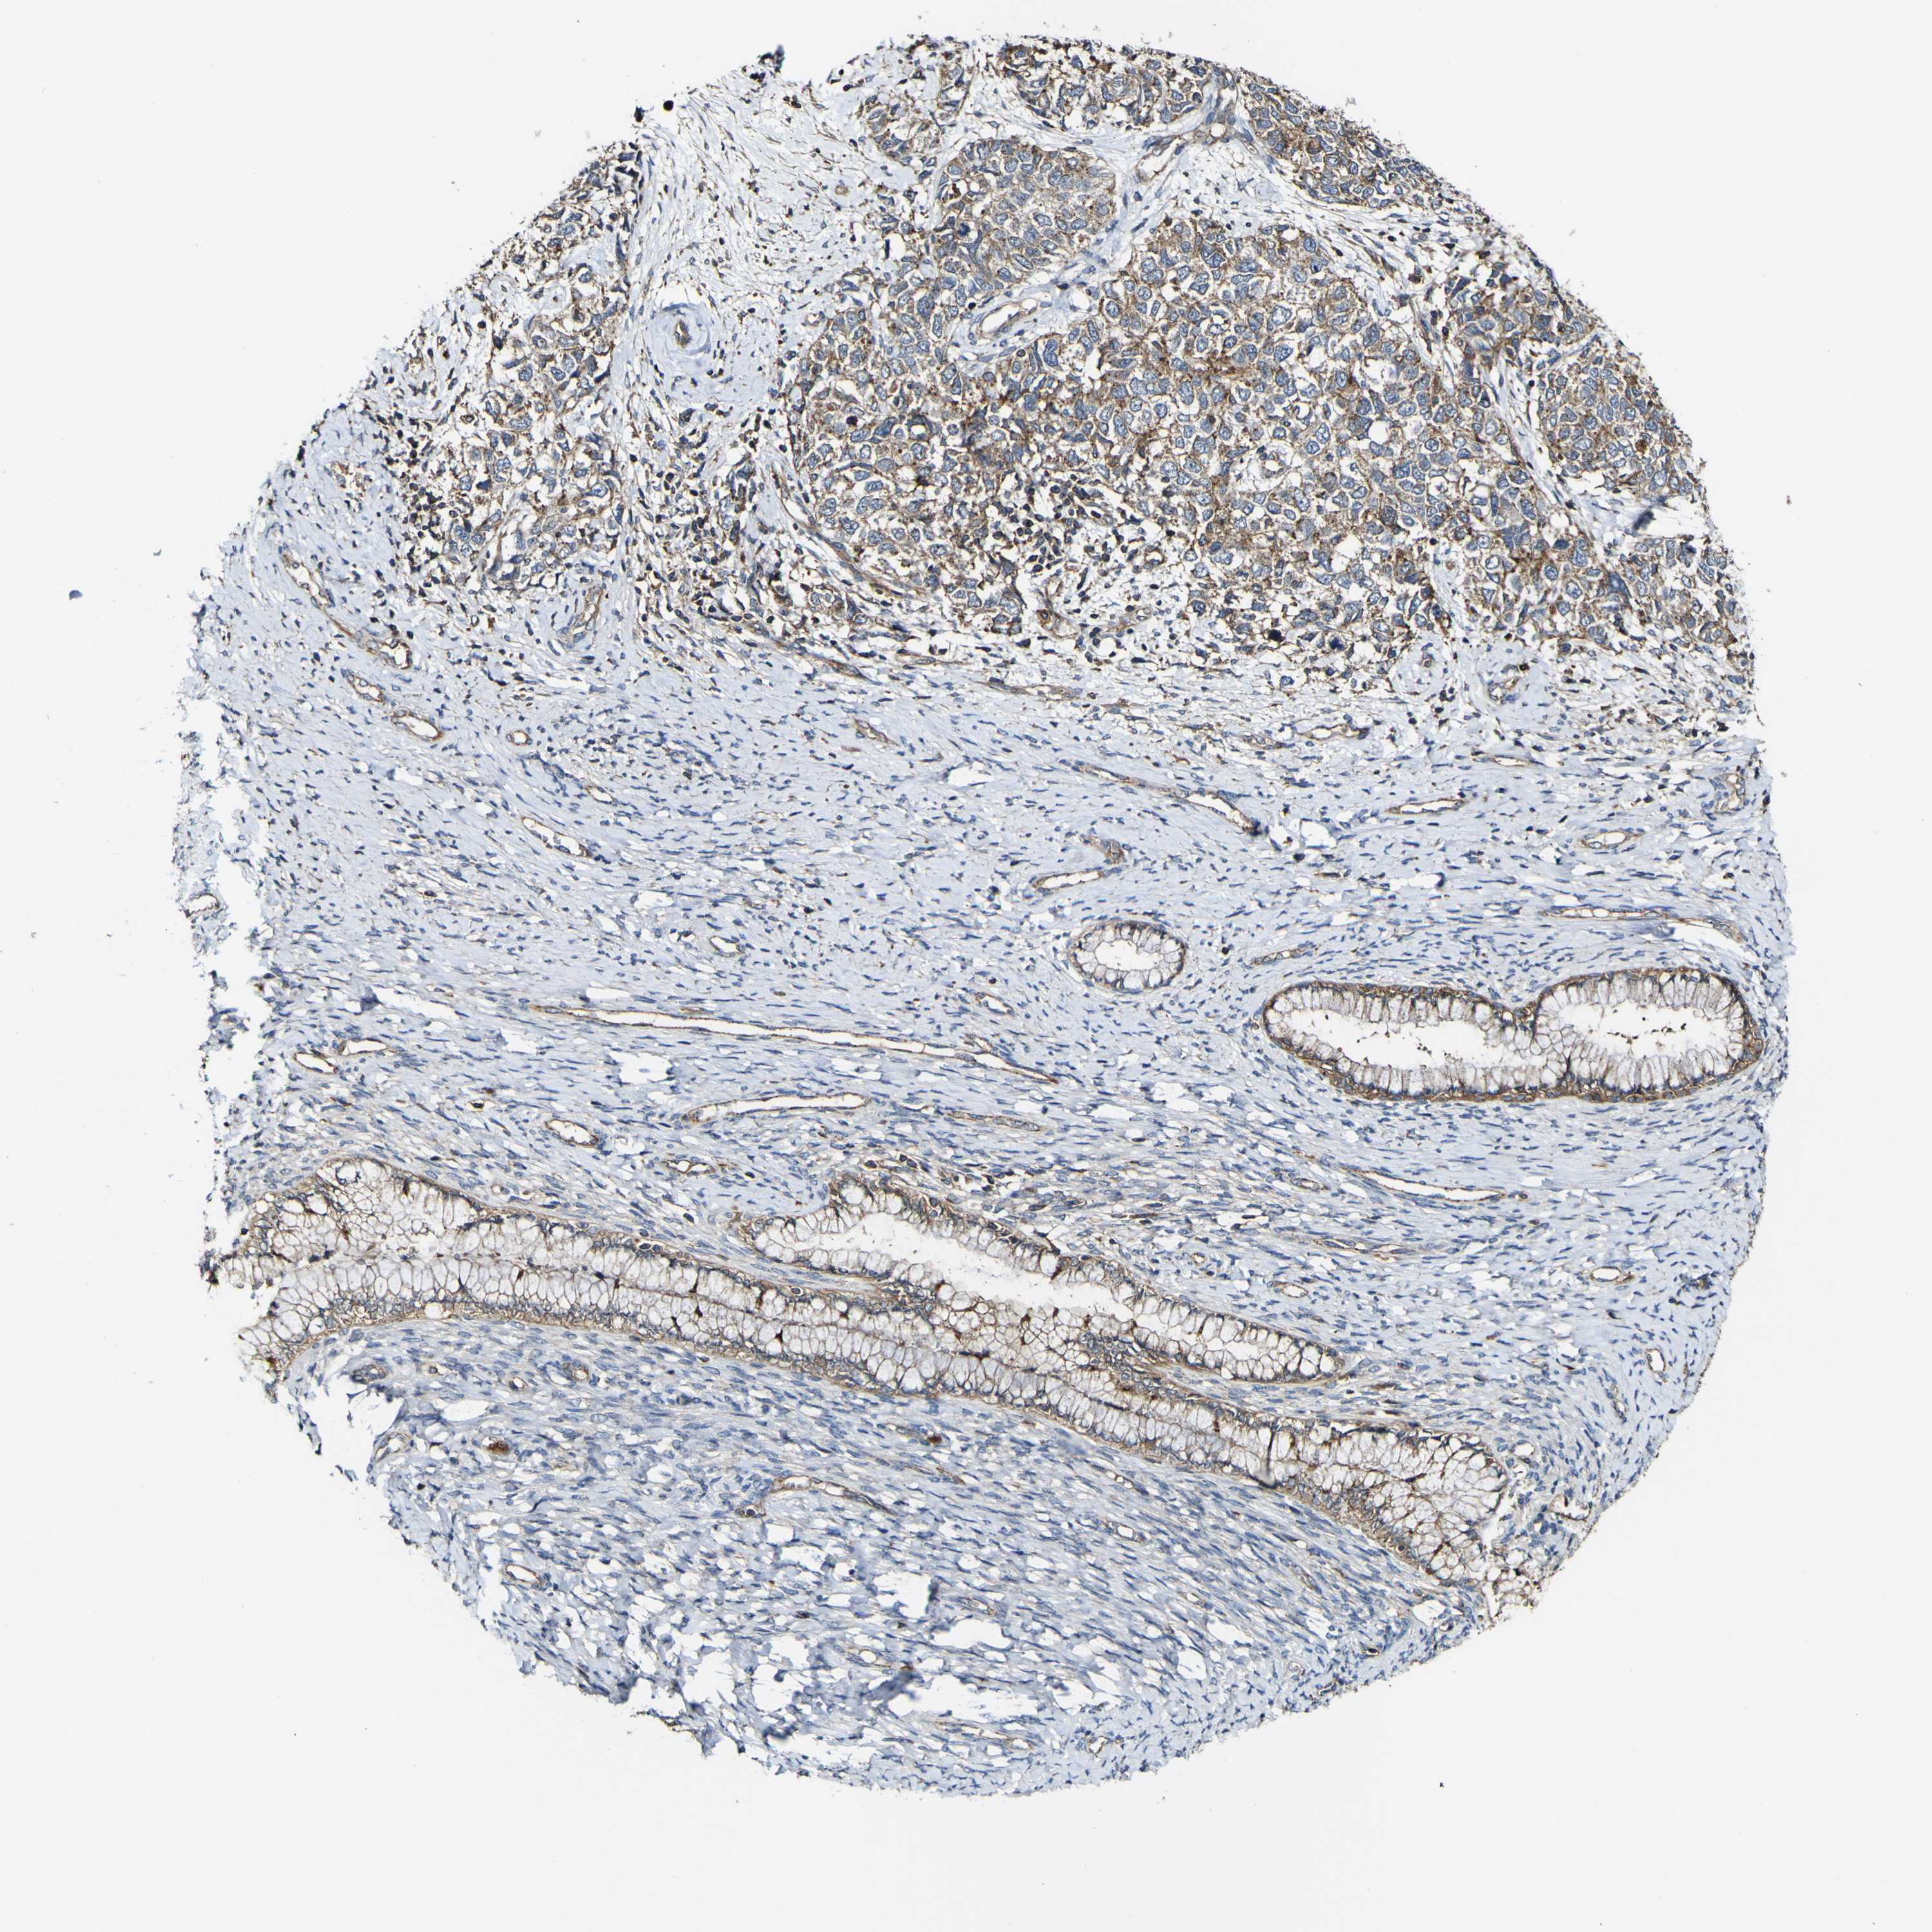

CERVICAL CANCER - Protein expressioni

A mouse-over function shows sample information and annotation data. Click on an image to view it in a full screen mode. Samples can be filtered based on level of antibody staining by selecting one or several of the following categories: high, medium, low and not detected. The assay and annotation is described here.

Note that samples used for immunohistochemistry by the Human Protein Atlas do not correspond to samples in the TCGA dataset.

Antibody stainingi

Antibody staining in the annotated cell types in the current human tissue is reported as not detected, low, medium, or high, based on conventional immunohistochemistry profiling in selected tissues. This score is based on the combination of the staining intensity and fraction of stained cells.

Each image is clickable and will lead to virtual microscopy that enables deeper exploration of all samples and also displays staining intensity scores, fraction scores and subcellular localization as well as patient and tissue information for each sample.

Antibody HPA012128

Antibody HPA012297

Staining

High

Medium

Low

Not detected

Intensity

Strong

Moderate

Weak

Negative

Quantity

>75%

75%-25%

<25%

None

Location

Nuclear

Cytoplasmic/membranous

Cytoplasmic/membranous,nuclear

Squamous cell carcinoma, NOS

Adenocarcinoma, NOS